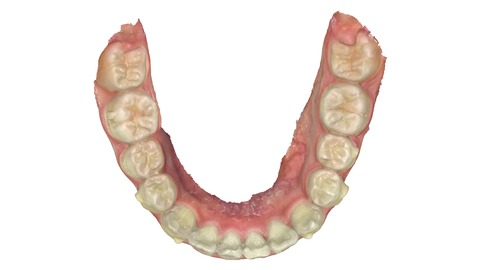

2025年1月5日 わずか9か月後の状態。

下の歯。こちらも歯並びの中に納まっている。

下の歯の比較

患者さんは平成23年生まれの13歳とあごの成長が残っている世代だった為、あごの成長をコントロールすることもできわずか10か月で終了することができた。